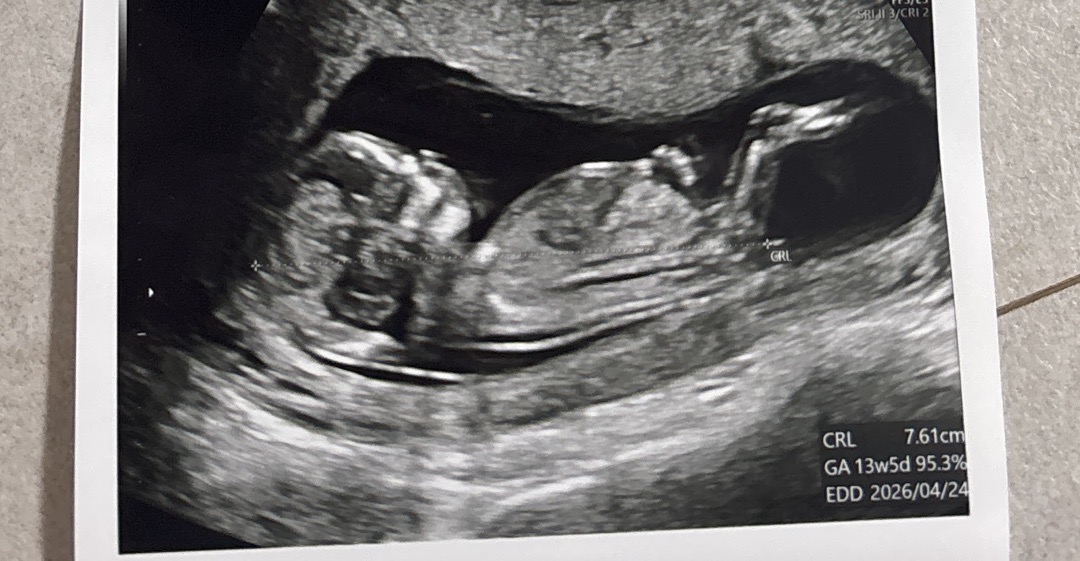

12주5일이에요! 각도법 봐주세요~

각도법으로 확인 가능할까요!? 아들일까요 딸일까요ㅠ